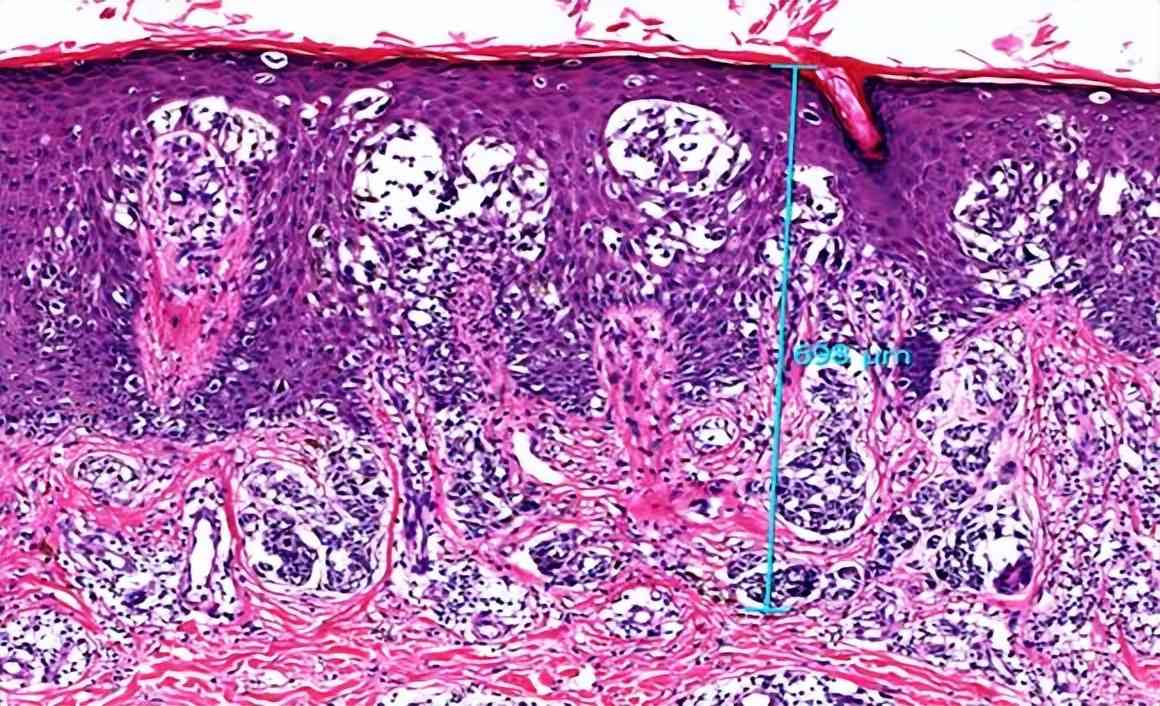

图2:误诊为Spitz痣的早期黑色素瘤病理图片

图4:图3的皮损。患者4年病史,切除前两年皮损无明显变化。免疫组化HMB45阴性,Ki-67 约3%。未用药,观察10年皮损未复发或出现转移。